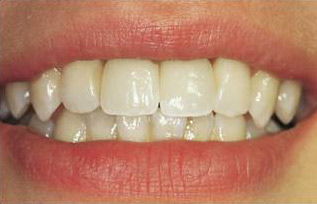

poslije

Fiksna protetka